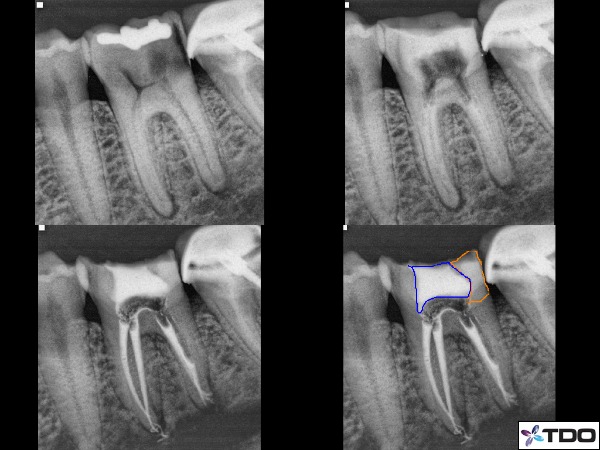

If the dentist wishes to remove the material we place they certainly can do that as well. Thankfully since just about all of these teeth will ultimately be prepared for a crown, maintaining the proximal contact is not a significant consideration and we typically leave that contact open. (Figure 3)

Fig. 3: Tooth #19 with significant proximal and occlusal decay under the alloy filling. I removed all decay and rebuilt the tooth with a composite filling with a bit of cotton covering the orifi of the canals (upper right x-ray). I then reaccessed into composite to remove the cotton and proceed with RCT. In this case I left a post space in one of the distal canals and the access is sealed with a temporary filling material. Lower right is an illustration with distal composite in orange and temporary material in blue.